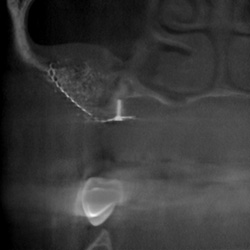

Elektrodenkontrolle nach

Cochlear Implantation